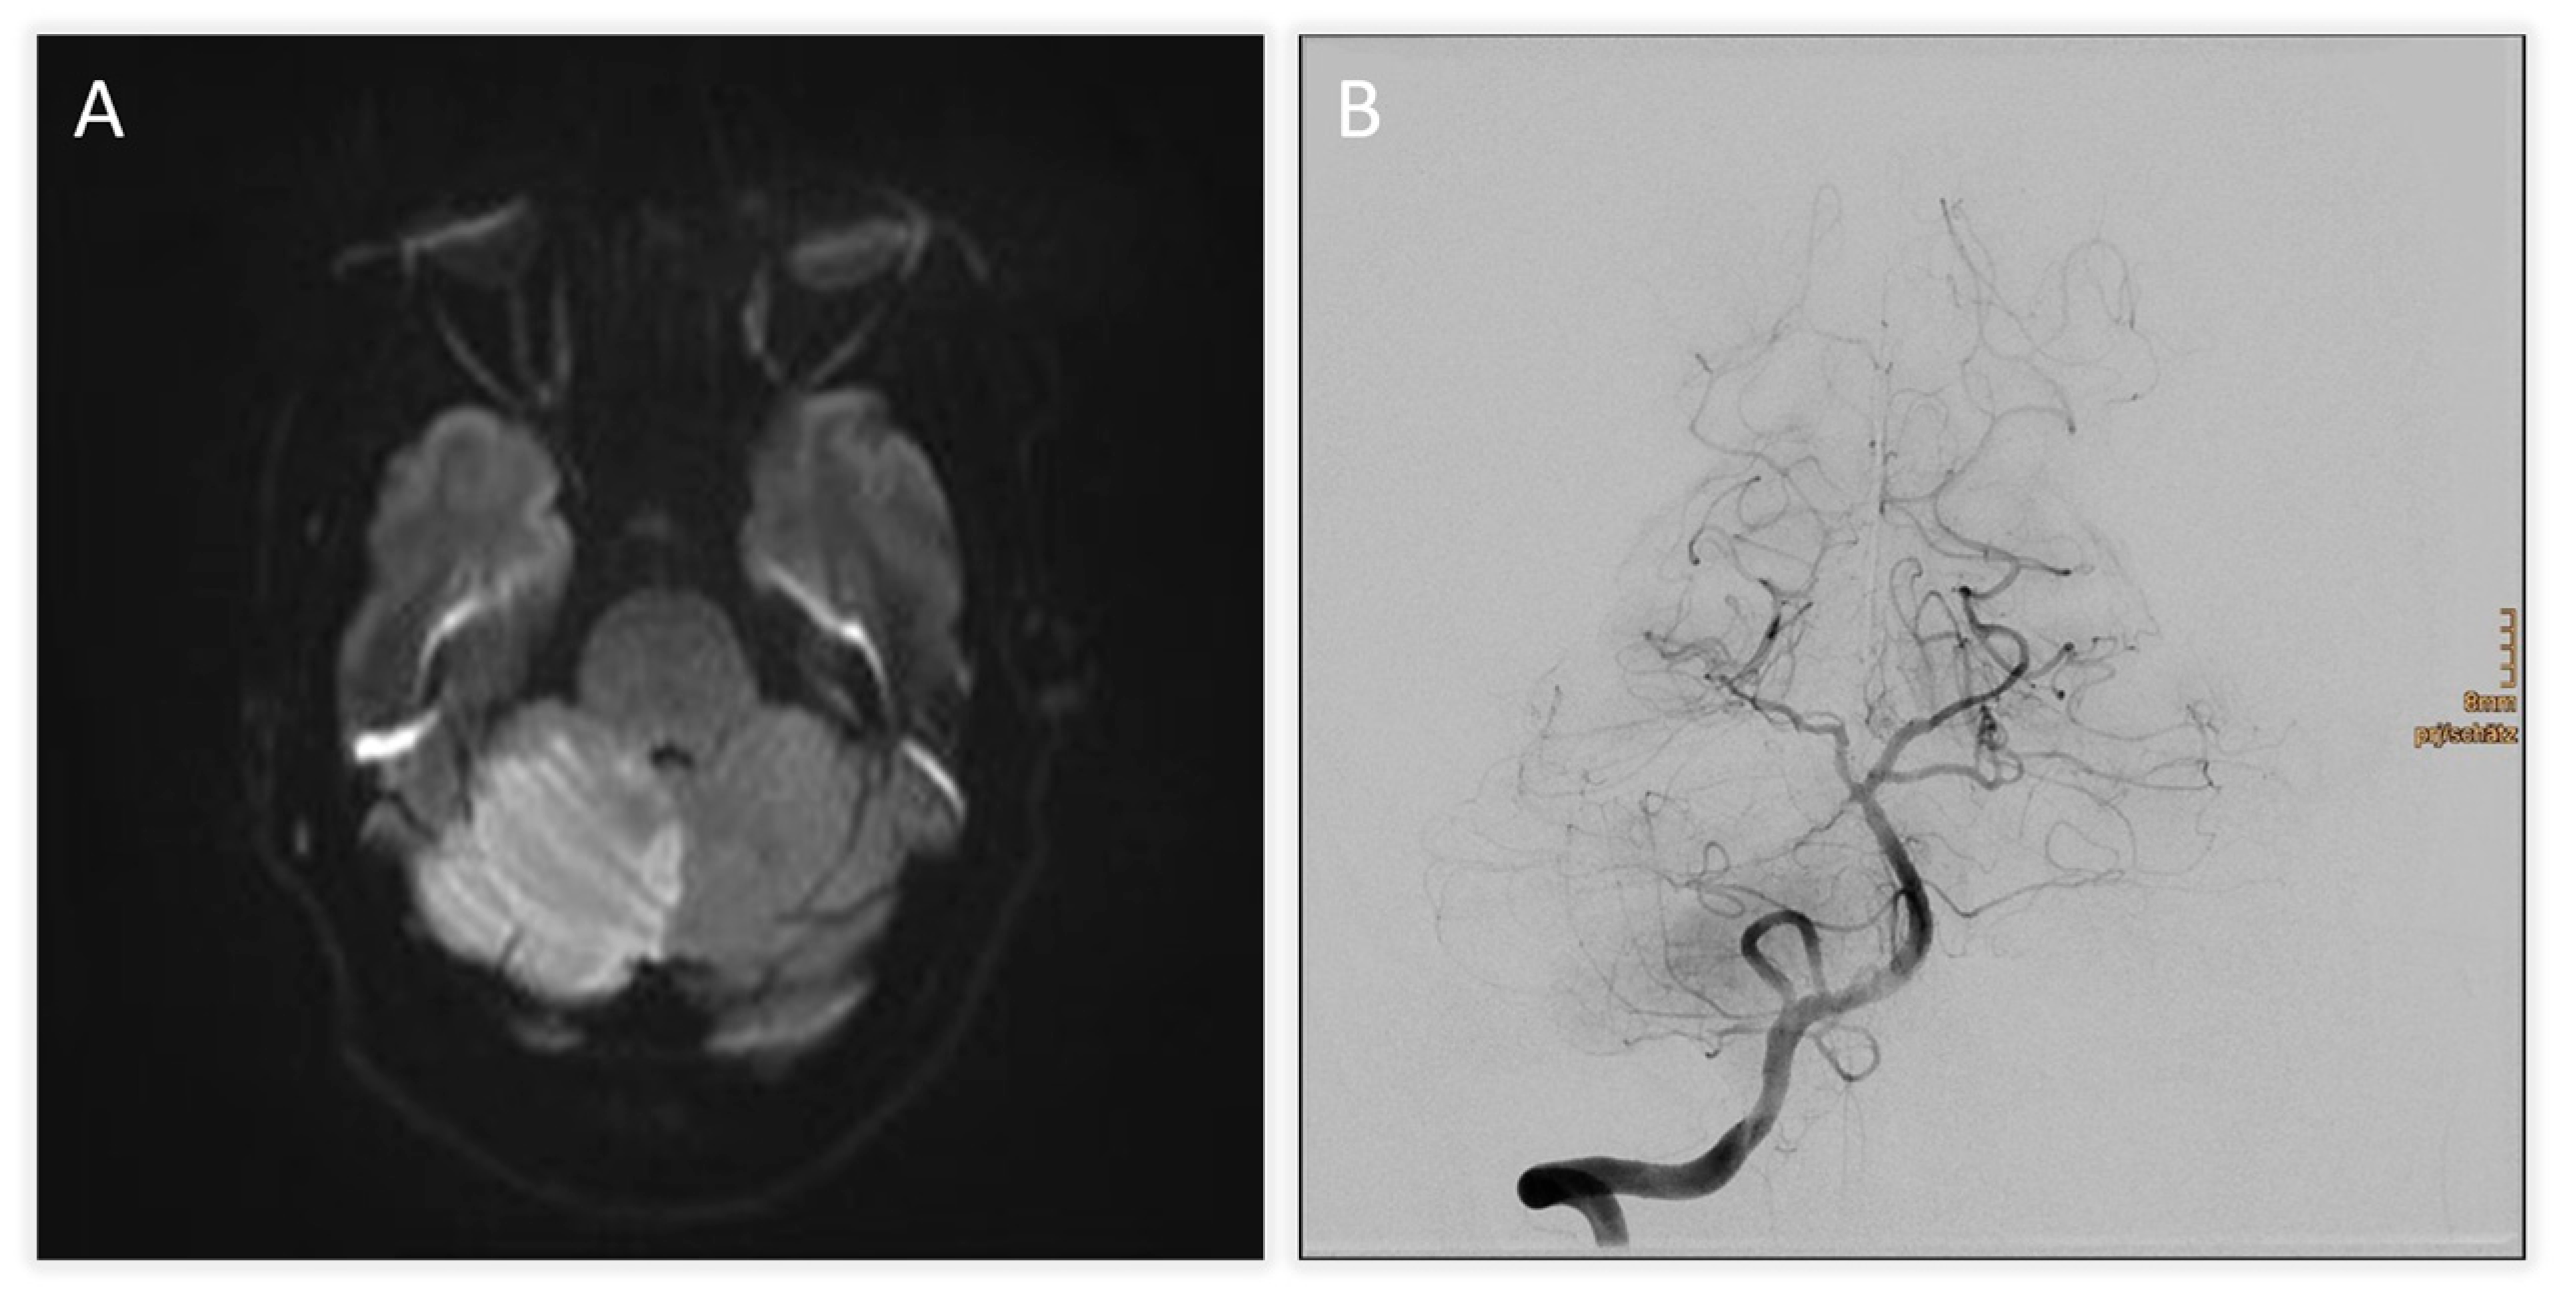

| +2 h (admission) | Initial MRI (DWI) + TOF-angiography | Acute infarction of right cerebellum and vermis; thrombus at basilar tip; right SCA occlusion |

| +4 h | Digital subtraction angiography (DSA) | Basilar tip patent, right SCA occluded; mechanical thrombectomy attempted but unsuccessful |